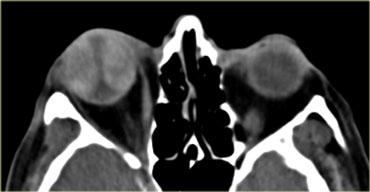

Áp xe quanh hốc mắt

Bên trái là hình ảnh CT không tiêm thuốc cản quang của một bệnh nhân có áp xe màng xương hoặc áp xe quanh hốc mắt rõ ràng do biến chứng của viêm xoang sàng.

Điểm cần lưu ý như sau:

Không cần chờ có viền ngấm thuốc ngoại vi mới chẩn đoán áp xe!

Ở các vị trí khác, chúng ta thường chờ có viền ngấm thuốc rõ ràng mới chẩn đoán áp xe, nếu không có thì gọi là viêm mô tế bào (phlegmone).

Điều trị là điều trị viêm xoang.Đây là hình ảnh MRI của một bé trai 11 tuổi, có biểu hiện kích thích mắt phải vào tối hôm trước và thức dậy với tình trạng lồi mắt.

Hình ảnh chuỗi xung T1W có tiêm thuốc tương phản từ kết hợp kỹ thuật xóa mỡ (fatsat) thể hiện rõ ràng áp xe quanh hốc mắt là nguyên nhân gây lồi mắt.

Lưu ý hình ảnh viêm xoang sàng.

Điểm quan trọng tiếp theo cần lưu ý là:

Ở trẻ em, cần hết sức thận trọng với sự lan rộng ra ngoài xoang!

Bất kỳ thay đổi nào bên ngoài xoang đều nên được chẩn đoán là áp xe.

Ở trẻ em, màng xương quanh hốc mắt có nhiều lỗ thông hơn và bệnh sẽ dễ dàng lan rộng.

Vì vậy, hãy mạnh dạn chẩn đoán áp xe ngay cả khi chỉ có những bất thường nhỏ.Áp xe quanh hốc mắt có thể dẫn đến huyết khối tĩnh mạch mắt trên và dưới.